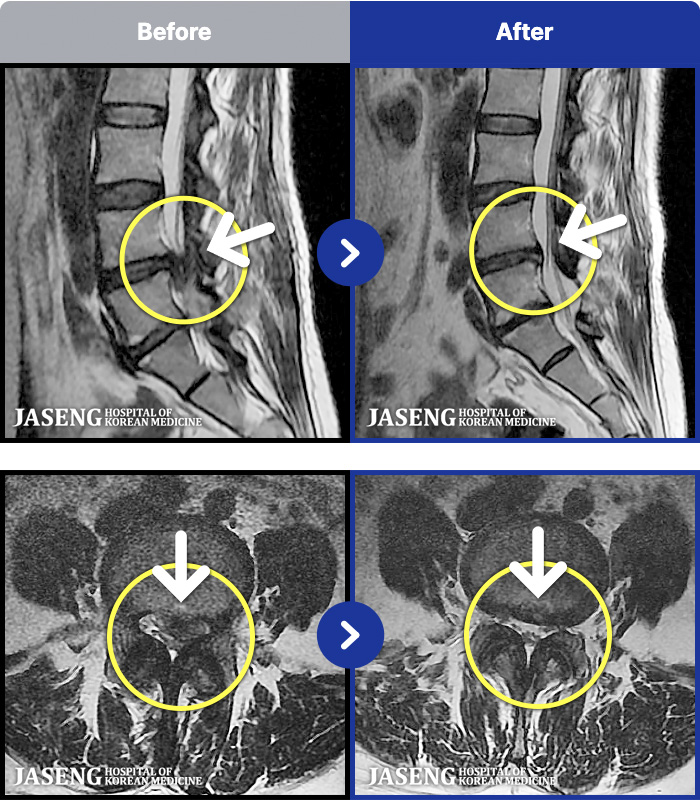

MRI ġ

1,243 MRI ũ ʸ Ȯϼ.